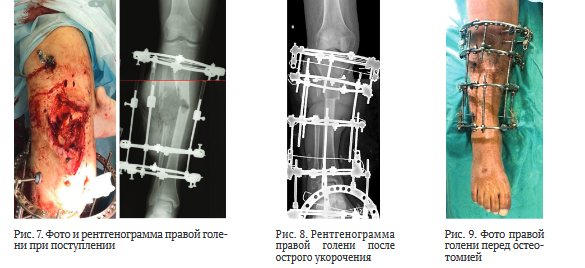

Пациент 44 лет (группа 2) получил ранение при участии в боевых действиях. Диагноз: Сочетанное взрывное поражение таза, обеих нижних конечностей. Множественные осколочные раны промежности, нижних конечностей. Обширная рваная рана правой голени, оскольчатый перелом обеих костей в верхней и средней трети с первичным дефектом костной и мягких тканей (рис. 7). Обширная рваная рана левой стопы с переломом 1 и 2 плюсневых костей. Острая массивная кровопотеря. Травматический шок 2 степени. Острое повреждение почек.

После стабилизации состояния и восстановления функции почек через 34 дня после ранения выполнили повторную хирургическую обработку раны, некрэктомию большеберцовой и малоберцовой костей, ОУ правой голени, ВЧКДО по Илизарову. Дефект большеберцовой кости составил 11 см (рис. 8).

Через 126 дней после ранения (на 92-е сутки после ОУ) выявили признаки сращения отломков и выполнили остеотомию в нижней трети большеберцовой кости (рис. 9 и 10, а).